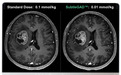

SubtleGAD可以广泛地适用于诸多医院,嵌入现有流程。SubtleGAD通过专利性深度学习算法,仅使用10%的钆(Gadolinium)基造影剂剂量,就可以达到往常全剂量MRI检测的同等效果与图像诊断质量。此外,SubtleGAD还可以改善图像质量,提高诊断准确率和病灶检出率。

图:左为常规剂量,右图中SubtleGAD将造影剂剂量降低了90%而不影响影像质量

据悉,该研究选取来自北京天坛医院的83例接受CE-MRI检查的患者数据。每一患者采集3套零剂量、低剂量(10%)、全剂量(100%) GBCA三维T1加权图像。研究表明在全部病例中,基于深度学习的图像重建与增强技术在临床中可获得良好的图像质量并准确匹配增强病变的数目,同时显著减少钆类造影剂的使用剂量高达90%,显示了该深度学习技术在磁共振检查中优化小剂量显影的巨大潜力。

此外,本月深透医疗团队另一篇论文也发表在顶级磁共振影响技术期刊《医学磁共振杂志》(Magnetic Resonance in Medicine)上。这些临床研究验证了SubtleGAD及其所采用的AI技术的有效性——它在不同医疗结构、不同的设备类型上用于处理了大量病人的医学影像——并且显示出在临床应用上未来的巨大的潜力和价值。两项研究论文对病灶检测以及肿瘤分割等方面进项了深入临床验证,同步论证了SubtleGAD可普遍适用不同神经系统疾病的影像增强,实现10倍于输入剂量的显影效果以及准确的病灶分析。

斯坦福大学放射科医生神经影像主任Max Wintermark教授表示:“SubtleGAD增强了低剂量图像的诊断质量,在临床上证明与我们研究中使用的10倍于低剂量的全剂量的图像相当。通过将SubtleGAD等新型AI产品纳入其AI产品体系中,影像中心将能够解决核磁共振成像检查中钆对比剂沉积的问题,从而使患者感到更加安心,并最终改善患者诊断质量与护理体验。”